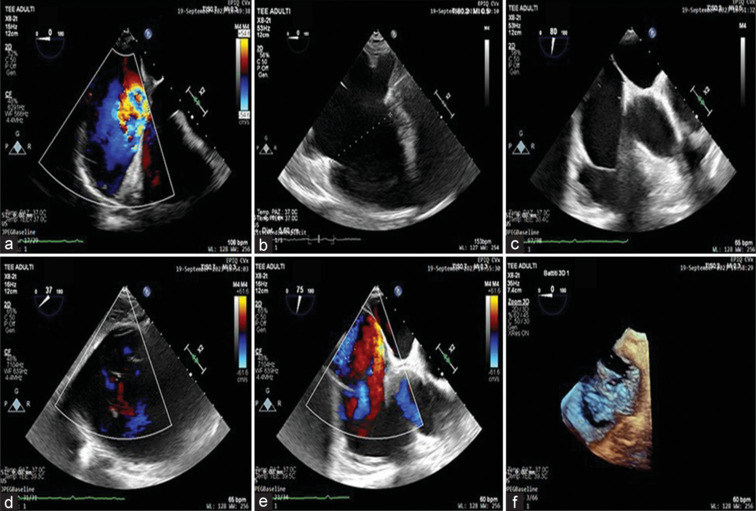

Tricuspid regurgitation (TR) is characterized by the backward flow of blood from the right ventricle to the right atrium during systole. It can be primary, involving intrinsic valve abnormalities, or secondary, due to deformation of the valve apparatus. This case is notable for severe TR following previously unreported chest trauma, emphasizing the importance of detailed medical history in diagnosing valvular conditions. A 62-year-old patient with right atrial and ventricular dilation was diagnosed with severe TR during a routine checkup. Echocardiography showed a prolapsed posterior tricuspid leaflet and annular dilation. Later, a prior chest trauma from a car accident was identified as the likely cause. This case highlights the need for a detailed history and echocardiography to assess TR severity, especially after chest trauma, to prevent right dysfunction and worsening outcomes.